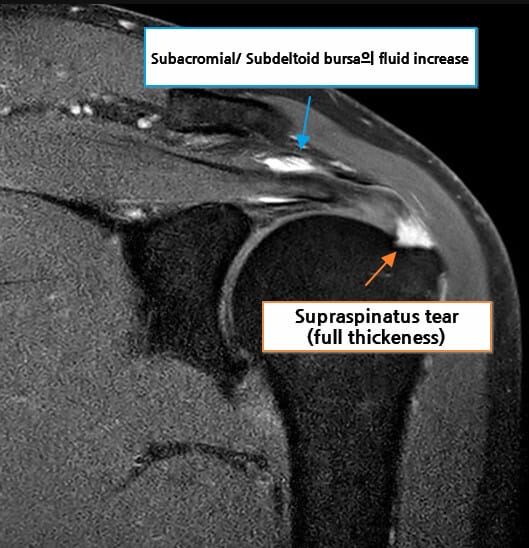

MRI (자기공명영상)

회전근개 힘줄의 부분 또는 완전 파열 여부, 파열 크기, 주변 근육의 지방 변성 및 위축 소견을 확인할 수 있습니다. 액체 음영이 파열 부위에 고여 있는 소견(fluid-filled gap)이 특징적입니다.